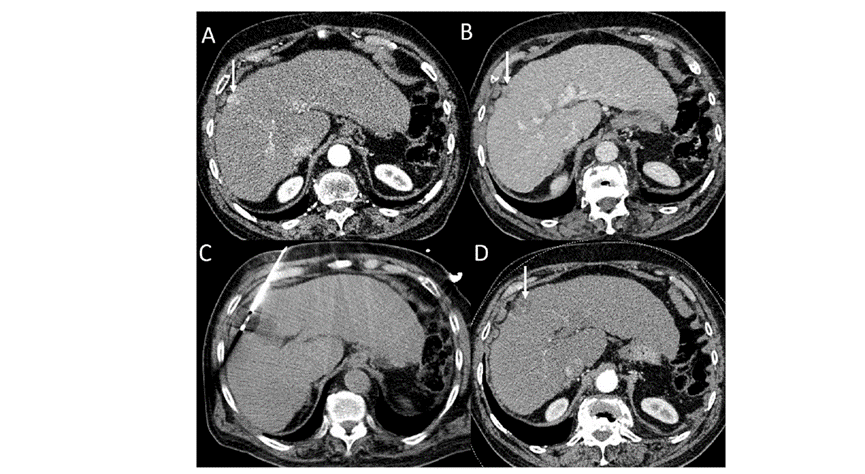

(A)動脈期CT圖像顯示有一個包膜下結(jié)節(jié)(箭頭)。(B)門靜脈期CT圖像顯示病灶區(qū)(箭頭)。(C) 在手術(shù)過程中的CT顯示一個冷凍探針位于病灶內(nèi)。(D)消融后,術(shù)后1個月影像CT顯示完全消融。患者在手術(shù)及住院期間無并發(fā)癥及重大并發(fā)癥發(fā)生。隨訪時間中位數(shù)為7個月(范圍:3-12個月),隨訪期間患者無局部腫瘤進展或死亡。

膽囊附近轉(zhuǎn)移灶(來自子宮頸癌)的冷凍消融術(shù)(A)門靜脈期 CT 圖像顯示膽囊附近有病變(箭頭)。(C) 手術(shù)過程中CT 顯示冷凍探針位于病灶內(nèi)。(D)消融手術(shù)后 1 個月CT 顯示完全消融。